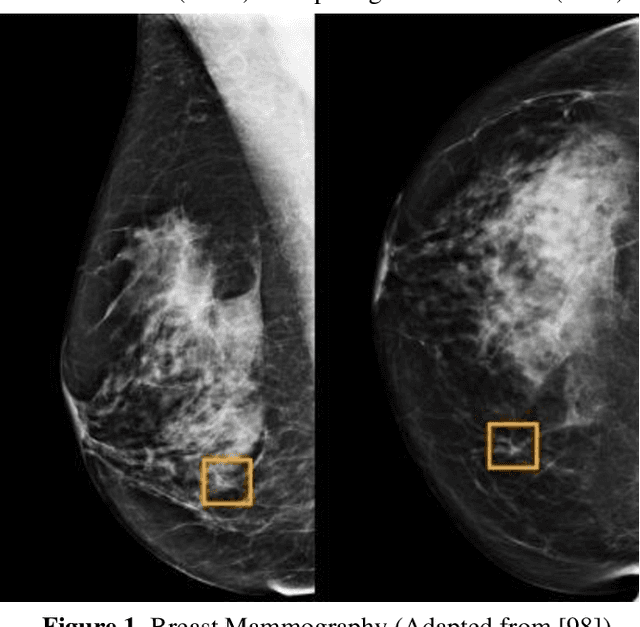

Abstract:Breast cancer is a common fatal disease for women. Early diagnosis and detection is necessary in order to improve the prognosis of breast cancer affected people. For predicting breast cancer, several automated systems are already developed using different medical imaging modalities. This paper provides a systematic review of the literature on artificial neural network (ANN) based models for the diagnosis of breast cancer via mammography. The advantages and limitations of different ANN models including spiking neural network (SNN), deep belief network (DBN), convolutional neural network (CNN), multilayer neural network (MLNN), stacked autoencoders (SAE), and stacked de-noising autoencoders (SDAE) are described in this review. The review also shows that the studies related to breast cancer detection applied different deep learning models to a number of publicly available datasets. For comparing the performance of the models, different metrics such as accuracy, precision, recall, etc. were used in the existing studies. It is found that the best performance was achieved by residual neural network (ResNet)-50 and ResNet-101 models of CNN algorithm.

Abstract:Breast cancer is a common cancer for women. Early detection of breast cancer can considerably increase the survival rate of women. This paper mainly focuses on transfer learning process to detect breast cancer. Modified VGG (MVGG), residual network, mobile network is proposed and implemented in this paper. DDSM dataset is used in this paper. Experimental results show that our proposed hybrid transfers learning model (Fusion of MVGG16 and ImageNet) provides an accuracy of 88.3% where the number of epoch is 15. On the other hand, only modified VGG 16 architecture (MVGG 16) provides an accuracy 80.8% and MobileNet provides an accuracy of 77.2%. So, it is clearly stated that the proposed hybrid pre-trained network outperforms well compared to single architecture. This architecture can be considered as an effective tool for the radiologists in order to reduce the false negative and false positive rate. Therefore, the efficiency of mammography analysis will be improved.